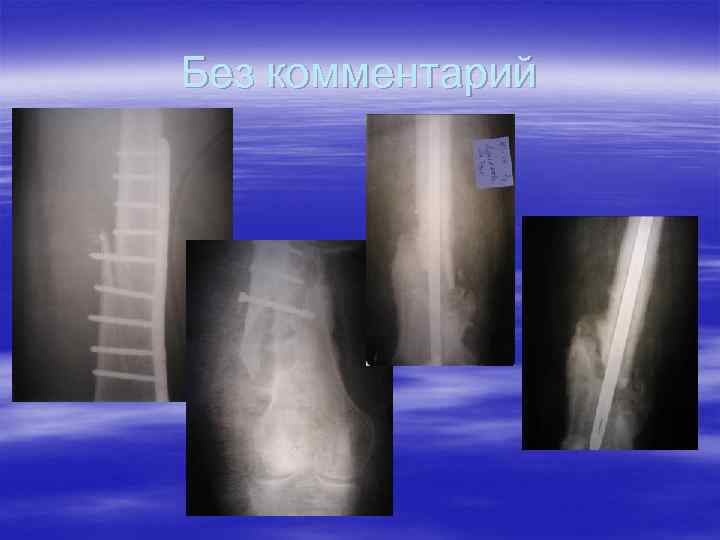

Без комментарий